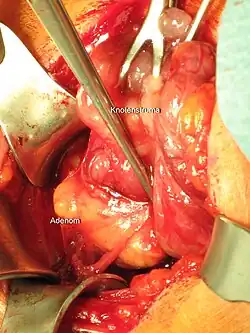

surgical photo of parathyroid gland removal

Parathyroidectomy for parathyroid adenoma

The patient is placed in a semi-Fowler position and the neck is extended. An abbreviated Kocher incision is made and the platysma muscle is dissected horizontally. The strap muscles are released off of the thyroid gland. Then the thyroid gland is mobilized and the parathyroid arterial blood supply is suture ligated. The entire parathyroid adenoma is identified and dissected out. Intra­operative PTH monitoring can begin at this time and will show falling PTH levels if the entire adenoma has been resected.‍[5]